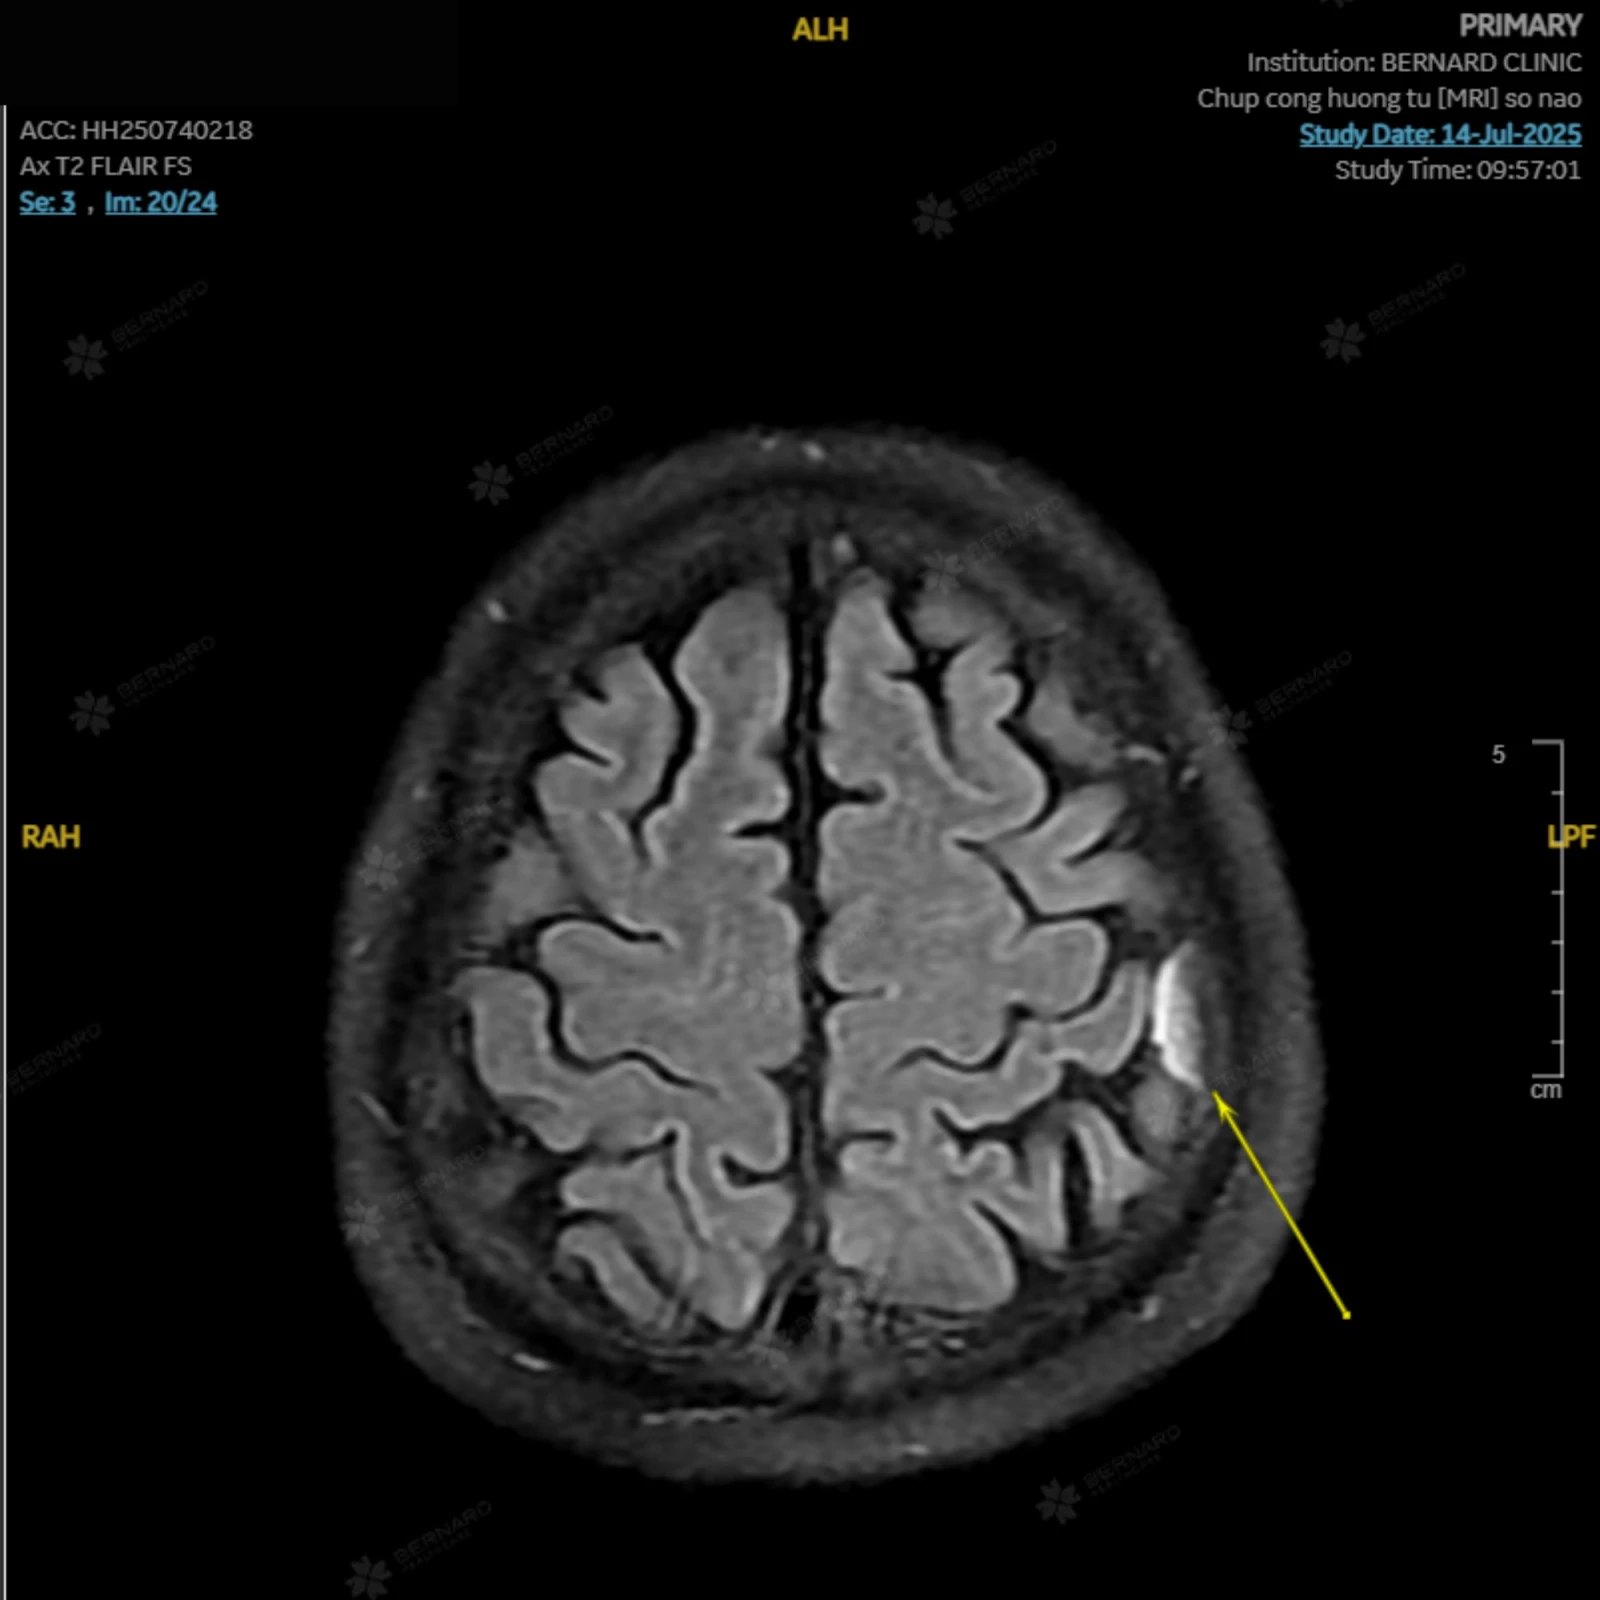

Kết quả phát hiện bất thường đáng lo ngại: Cấu trúc dạng choán chỗ ngoài trục đỉnh trái, kích thước #10x20x16mm (ngang x trước sau x cao), gợi ý u màng não nhỏ.

Theo đánh giá của bác sĩ Bernard, khối u hiện diện ở nam bệnh nhân có kích thước nhỏ, nhiều khả năng là lành tính, chưa gây ra triệu chứng ảnh hưởng đến sức khỏe nên chưa cần can thiệp ngay, có thể trì hoãn phẫu thuật. Dù vậy, bệnh nhân vẫn cần được theo dõi sát sao, tái khám định kỳ và chú ý theo dõi các triệu chứng bất thường để kịp thời xử trí, phòng ngừa các biến chứng.